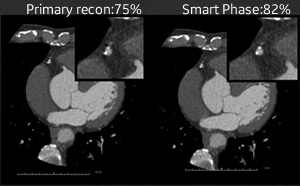

201704_voice_img_ct_02_04.jpg

図3. Smart Phase

3本の独立した冠動脈をそれぞれ抽出し、そのアーチファクト量から自動で最適静止位相を検索する機能であり、画像処理時間の大幅な短縮が可能となった。(図2、3)